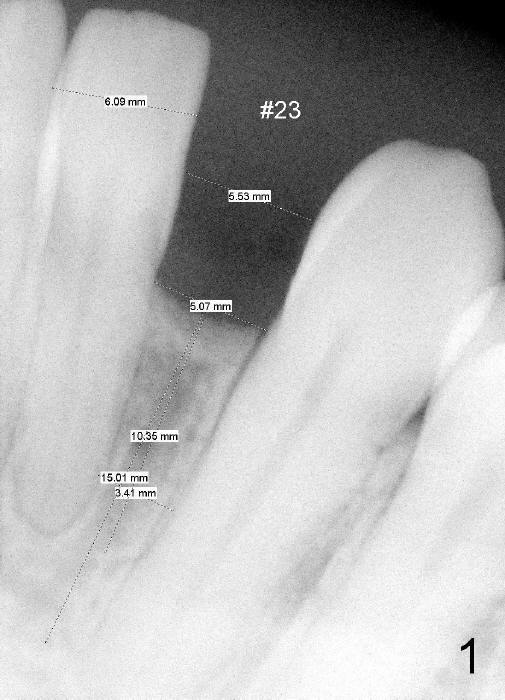

Informed consent is obtained with emphasis of potential damage to the neighboring roots.  Two PAs have to be taken with the first pilot drill (1.5 mm) in place for determination of initial trajectory (Fig.2,3).  Osteotomy is enlarged coronally with 2 mm pilot drill.  Finally a 3x17 mm one piece implant is placed with primary stability, determined tactilely (Fig.4).  Immediate provisional is fabricated.  To avoid micromovement, the immediate provisional (Fig.5 P) is bonded to the neighboring teeth with composite (*); it is further fixed in place with a lingual retainer (Fig.6 arrowhead).